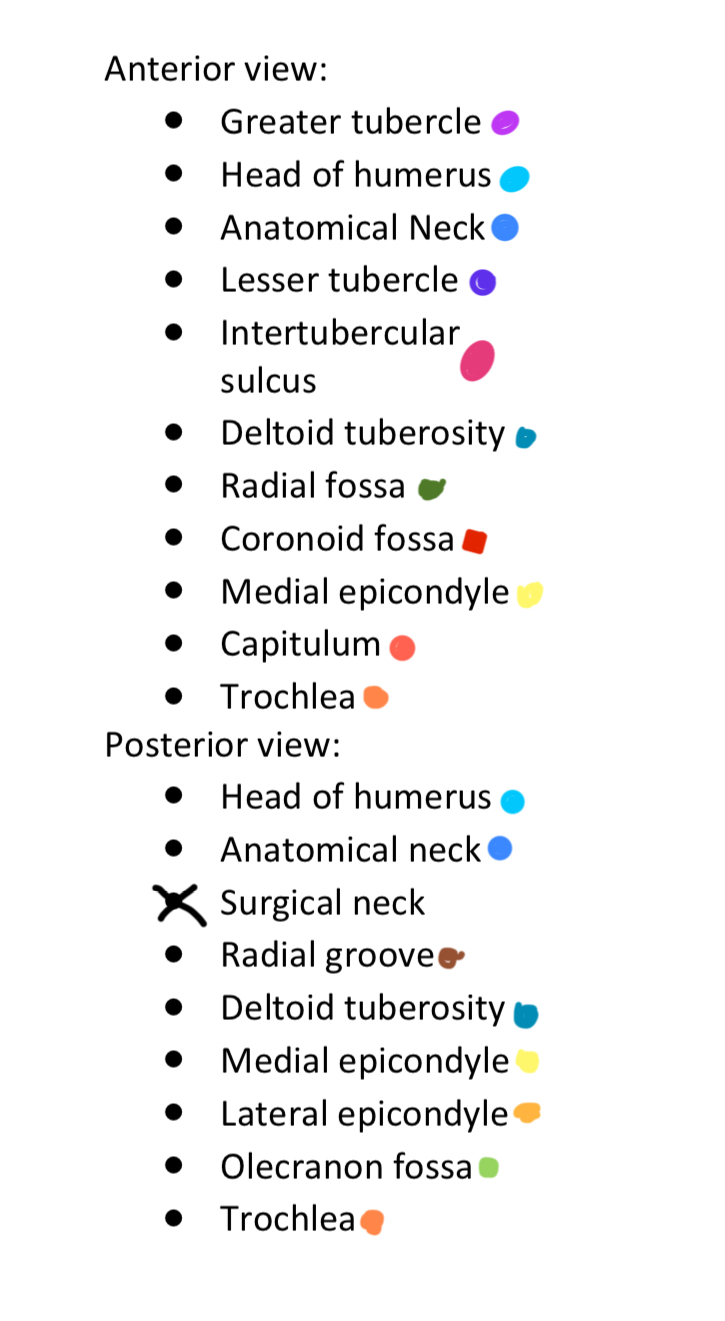

Anterior & Posterior Views of the Humerus

14 Terms

1

New cards

Light Purple

Greater Tubercle

2

New cards

Light Blue

Head of Humerus

3

New cards

Dark Blue

Anatomical Neck

4

New cards

Dark Purple

Lesser Tubercle

5

New cards

Pink

Intertubercular Sulcus

6

New cards

Cyan

Deltoid Tuberosity

7

New cards

Dark Green

Radial Fossa

8

New cards

Red

Coronoid Fossa

9

New cards

Yellow

Medial Epicondyle

10

New cards

Salmon

Capitulum

11

New cards

Dark Orange

Torchlea

12

New cards

Brown

Radial Groove

13

New cards

Light Orange

Lateral Epicondyle

14

New cards

Light Green

Olecranon Fossa